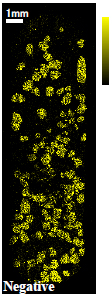

カプセル剤タイプ薬の断面についてTOF-SIMSによる質量イメージング分析を行いました。断面加工を行い、薬剤全体(約7mm×20mm)とその内部の顆粒一粒(約500μmΦ)に着目したイメージング事例をご紹介します。

光学顕微鏡像とTOF-SIMSイメージング

| 光学顕微鏡 | ●成分A | ■成分B | ▼成分C | |

●成分A:イブプロフェン

■成分B:デキストロメトルファン臭化水素酸塩水和物

▼成分C:無水カフェイン